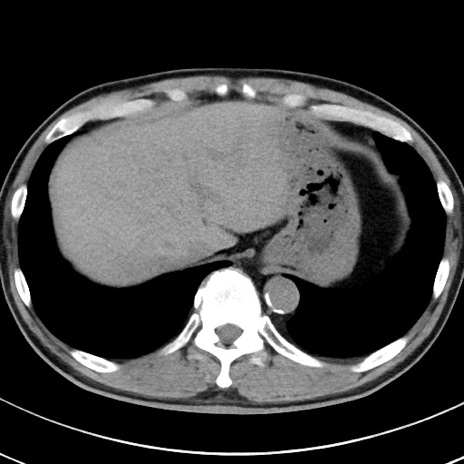

【腹部TIPS】症例29 参考症例 CT(横断像)

症例

70歳代男性